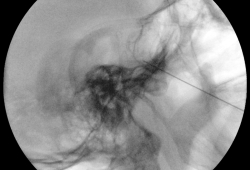

Een fijne naald wordt geplaatst richting het ganglion via het wanggebied, onder röntgendoorlichting. Vervolgens wordt u kort wakker gemaakt om elektrische stimulaties te beoordelen. Op basis van uw feedback over het pijngebied, wordt de juiste zenuwtak geïdentificeerd.

Daarna wordt u opnieuw in slaap gebracht en wordt met radiofrequente stroom een kleine letselzone aangebracht in het ganglion. Dit proces wordt indien nodig herhaald tijdens dezelfde sessie.